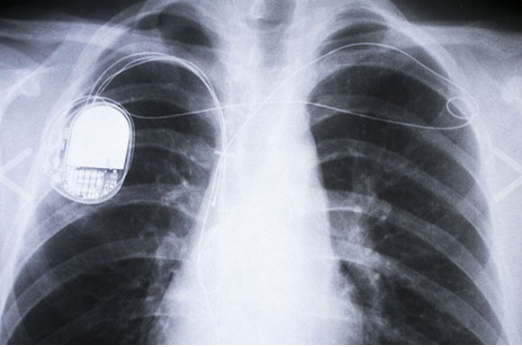

윌슨 그레이트베취는 전기 회로에 지칠 줄 모르는 관심을 갖고 있던 인물로, 심 블록을 치유하는 자연적인 방법에 대해 획기적인 아이디어를 가지게 되었습니다. 심 블록은 심장 주변의 신경에서 혈액 발송을 위한 신호를 받지 않게 되는 증상입니다. 이 증상의 치료를 목표로 한 것은 아니었던 그가 대발견을 한 순간은, 코넬 대학에서 심장 박동을 기록하는 발신기를 개발하고 있던 때였습니다.

1958년, 그는 잘못된 트랜지스터를 손에 들고, 장치에 조립하게 됩니다. 바로 실수를 깨달았지만, 그 결과에는 관심이 끌렸습니다. 스위치를 넣어 보니, 귀에 익은 리듬이 들려옵니다... 심장 박동과 비슷한 패턴입니다. 그리고 동물 실험을 거쳐 인간에서 시험된 것은 1960년의 일입니다.

※심장 페이스메이커

부정맥과 서맥 치료에 사용되는 기기